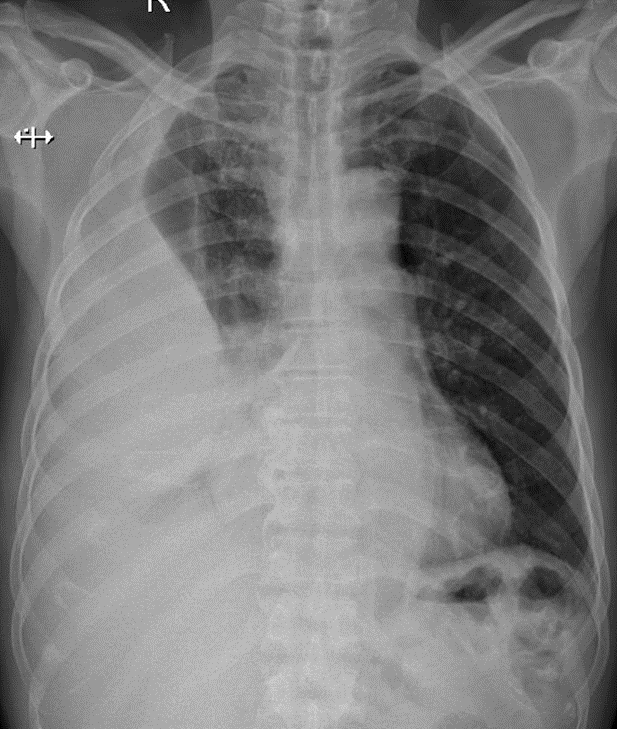

Hãy phân tích tình huống nam 91 tuổi

1-Tràn dịch màng phổi (P) lượng trung bình